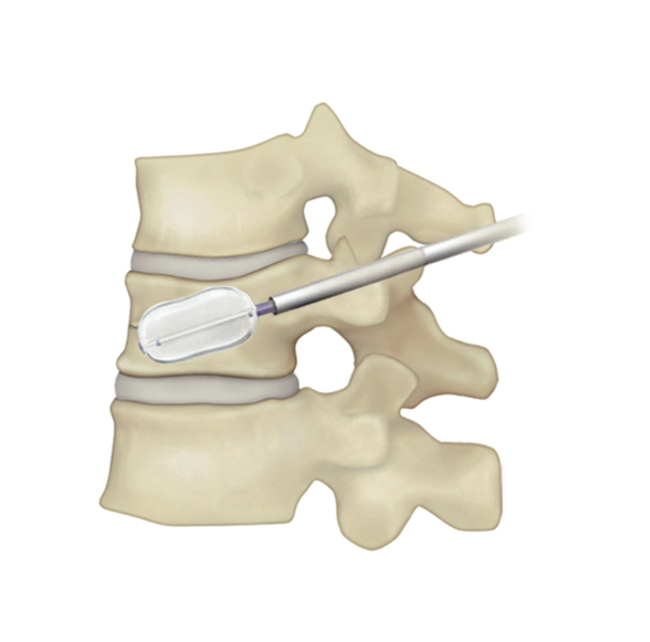

BKP治療手術の流れ

| 1)背中から針を刺入し骨折した椎体への経路を作成。小さな風船の付いた器具を挿入。 | 2)風船を徐々に膨らませつぶれた骨を持ち上げ骨折前の形に戻す。 | 3)風船を抜いて、その空間に骨セメントを充填する。 | 4)手術は約1時間程度。セメントは手術中に固まる。 |